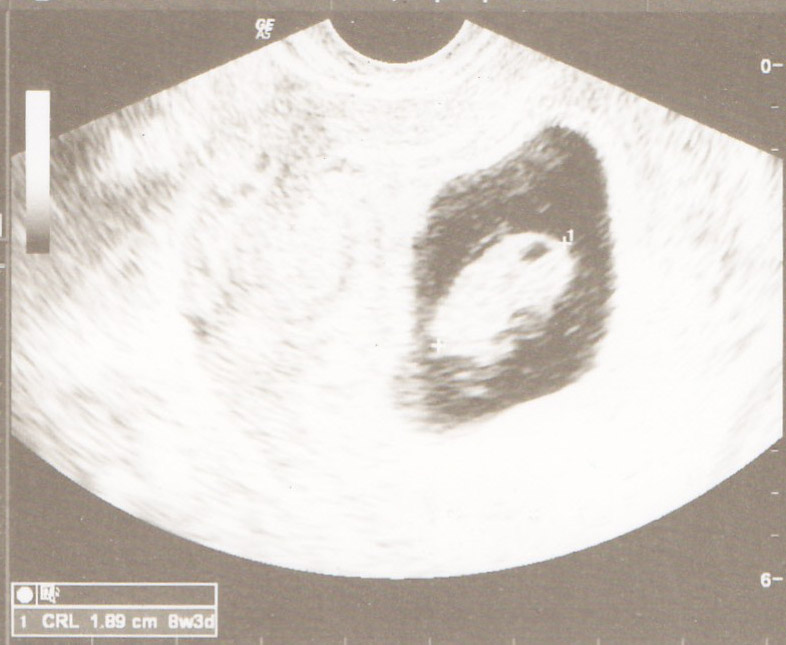

I just found out I was pregnant this week and we had our first ultrasound yesterday to find out how far along. I am 8 weeks and 3 days due June 22nd. Heart rate was 156.